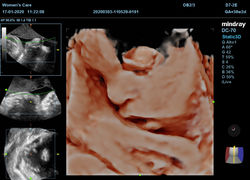

Ultrasonido 3D y 4D